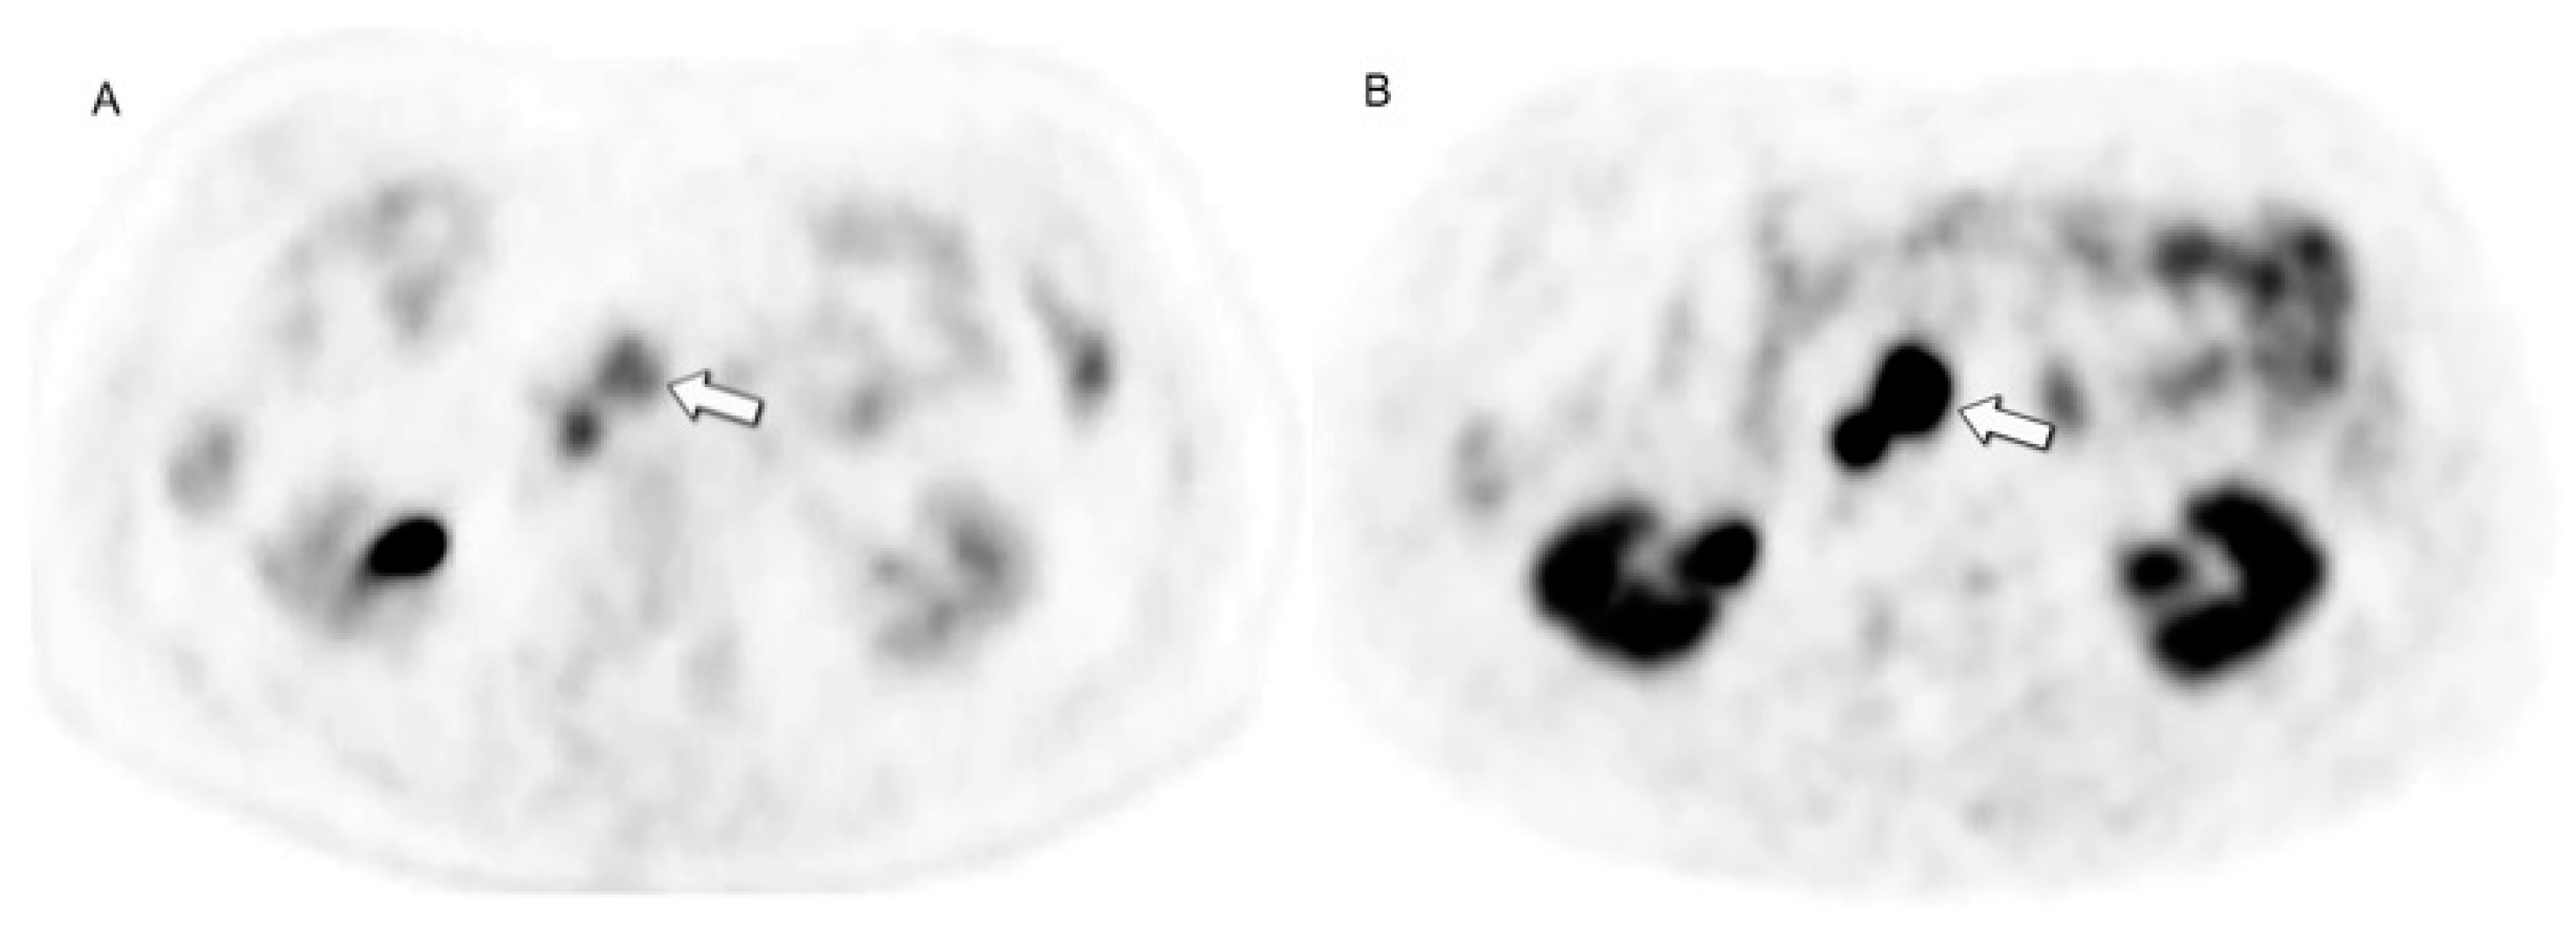

- Karfis, I.; Marin, G.; Levillain, H.; Drisis, S.; Muteganya, R.; Critchi, G.; Taraji-Schiltz, L.; Guix, C.A.; Shaza, L.; Elbachiri, M.; et al. Prognostic Value of a Three-Scale Grading System Based on Combining Molecular Imaging with 68Ga-DOTATATE and 18F-FDG PET/CT in Patients with Metastatic Gastroenteropancreatic Neuroendocrine Neoplasias. Oncotarget 2020, 11, 589–599. [Google Scholar] [CrossRef] [PubMed]